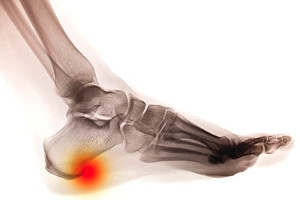

A heel spur is a bony growth on the calcaneus, or heel bone, that often extends into the arch of the foot. Though this can become painful, many people have heel spurs and are unaware of them. Heel spurs are often associated with plantar fasciitis, which is the inflammation of the band of tissue that connects the heel to the ball of the foot. Heel spurs, which are calcium deposits, develop over a period of time. They can be the result of continual stretching of the plantar fascia or repeated tearing of the membrane that covers the heel bone. Heel spurs are especially common among runners and other athletes who do a lot of jumping. Other risk factors are running on hard surfaces, footwear that does not provide proper heel cushioning or arch support, and excess weight or obesity. In addition, people who spend a great part of the day on their feet may be more likely to develop heel spurs. Seniors, people with diabetes, and anyone with arch problems also may be more at risk. If heel spurs are causing pain and interfering with your daily activities, it is suggested that you consult a podiatrist for an exam and treatment options.

Heels Spurs

Heel spurs are formed by calcium deposits on the back of the foot where the heel is. This can also be caused by small fragments of bone breaking off one section of the foot, attaching onto the back of the foot. Heel spurs can also be bone growth on the back of the foot and may grow in the direction of the arch of the foot.

Older individuals usually suffer from heel spurs and pain sometimes intensifies with age. One of the main condition's spurs are related to is plantar fasciitis.

Pain

The pain associated with spurs is often because of weight placed on the feet. When someone is walking, their entire weight is concentrated on the feet. Bone spurs then have the tendency to affect other bones and tissues around the foot. As the pain continues, the feet will become tender and sensitive over time.